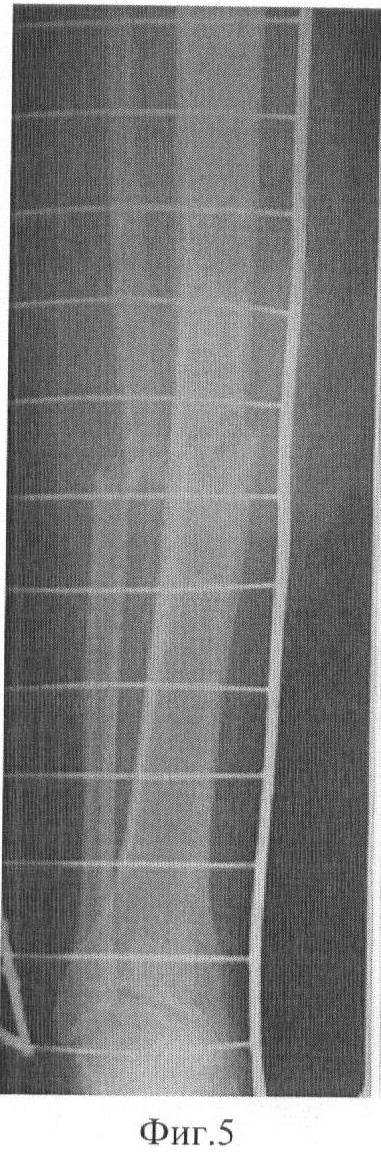

Фиг.5 Фоторентгенограммы больного до операции: прямая проекция;

Демонстрируем сказанное клиническим наблюдением. Больной С-ов, 18 лет, история болезни 12608/2008. В результате ДТП получил оскольчатый перелом средней трети обеих костей правой голени со смещением фрагментов (Фиг.5 и 6). Выполнен чрескостный остеосинтез аппаратом внешней фиксации. Вначале были проведены базовые чрескостные элементы и смонтирована рама аппарата (Фиг.1). Затем смещение фрагментов было устранено с помощью стержней-шурупов (Фиг.2). При этом возникли деформация и напряжение базовых чрескостных элементов. Были введены стабилизирующие стержни-шурупы (Фиг.3). После этого, не опасаясь вторичного смещения фрагментов, базовые чрескостные элементы были переустановлены (Фиг.7 и 8). Период фиксации составил 103 дня. Осложнений (вторичного смещения фрагментов, воспаления мягких тканей в области выхода чрескостных элементов) отмечено не было (Фиг.9 и 10). Через неделю после снятия аппарата внешней фиксации (Фиг.11-14) больной приступил к труду.